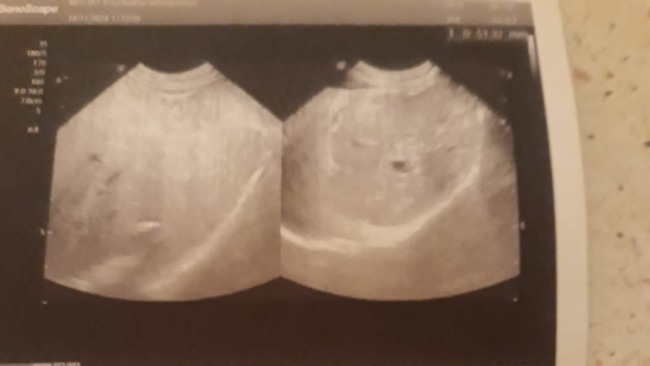

Jest jednak szansa dla Saszy. Trzeba jak najszybciej zrobić tomograf jamy brzusznej. Pokaże on dokładną strukturę nowotworu, wykluczy lub potwierdzi zmiany przerzutowe, pokaże dokładny umiejscowienie dużo bardziej dokładniej niż w obrazie USG . Dzięki temu jest szansa na operację.

Ostatnie wizyty były bardzo ciężkie. Okazało się że na wątrobie Saszy pojawił się guz nowotworowy. Jest umiejscowiony w bardzo złym miejscu, na płacie przylegającym do pęcherzyka żółciowego. Ma około 5 cm i jak na razie nie rośnie.